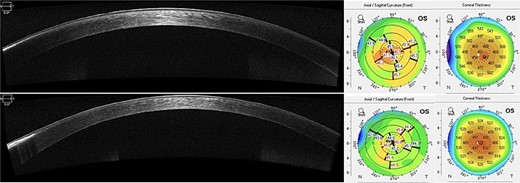

Scheimpflug imaging (Pentacam HR, Oculus Wetzlar, Germany) revealed irregular astigmatism, as shown by sagittal curvature maps and anterior elevation maps, with a central corneal thickness of 461 μm (Fig. 3).

Scheimpflug imaging showing irregular astigmatism and superficial irregularity.